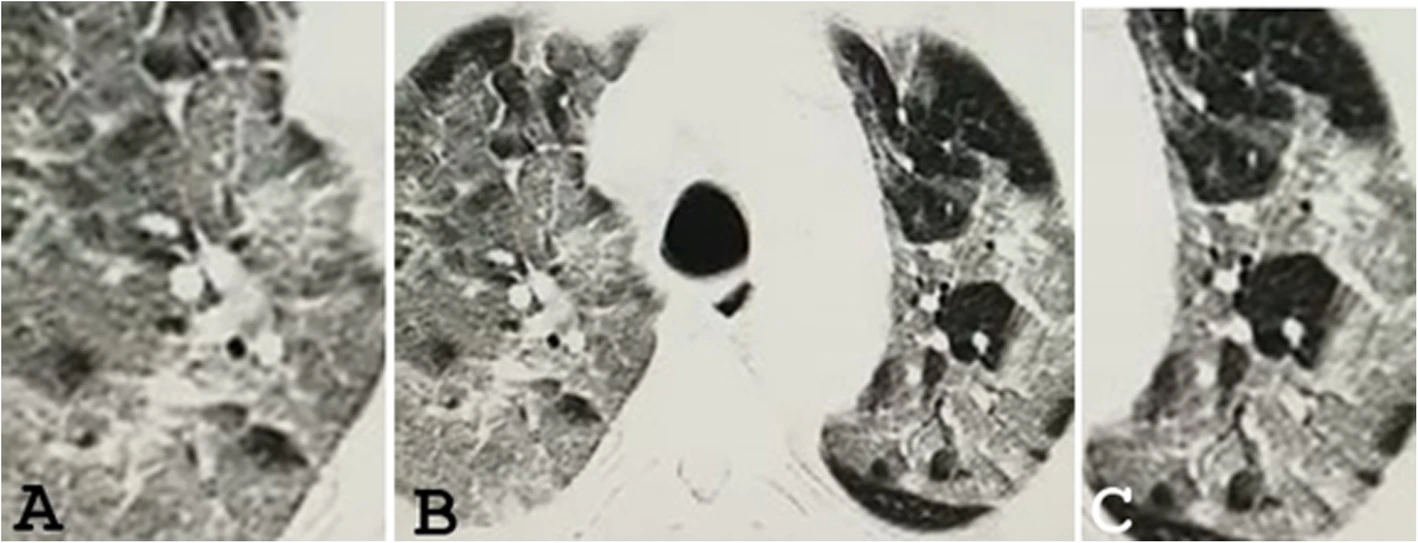

COVID-19 CT Scans

37 yrs

52 yrs

73 yrs

ground-glass opacity (GGO)